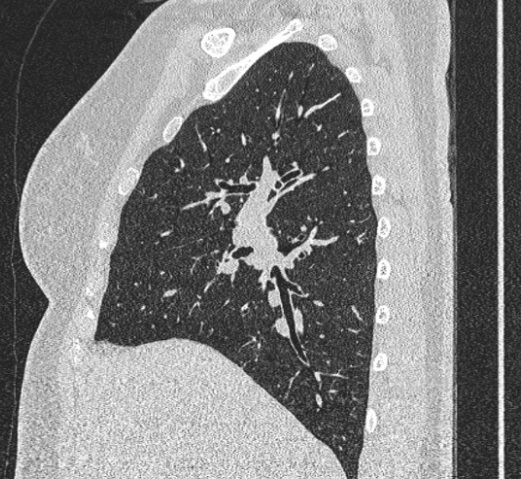

Image radiologique TDM normale du poumon

en coupe sagital , fenetre parenchymateuse |